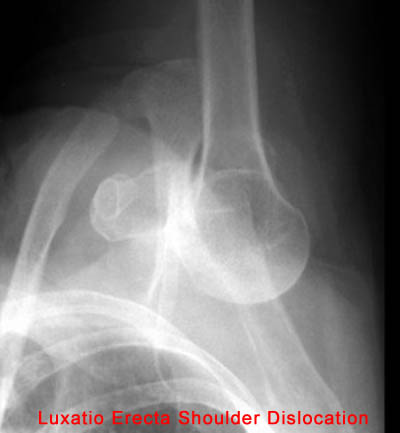

15) Name the abnormality shown in the image below.

16) What anatomical structure can be easily damaged during a dislocation such as the one shown above?

Neurovascular Bundle